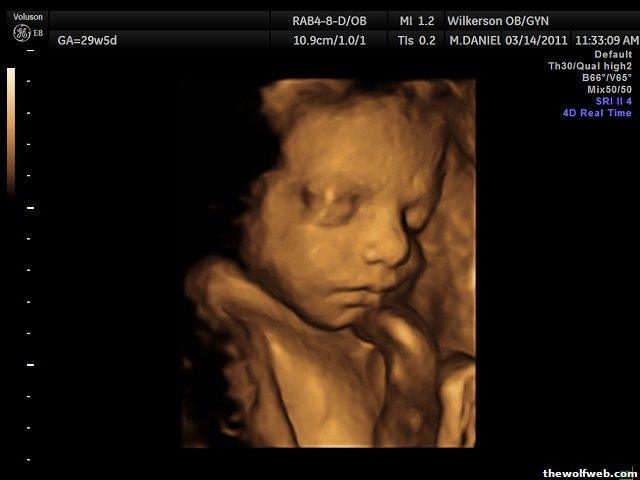

To cheer everyone up, here are pictures from our 3D/4D yesterday.

Estimated Fetal Weight 3lb11oz @ Estimated GA 29wk5dy